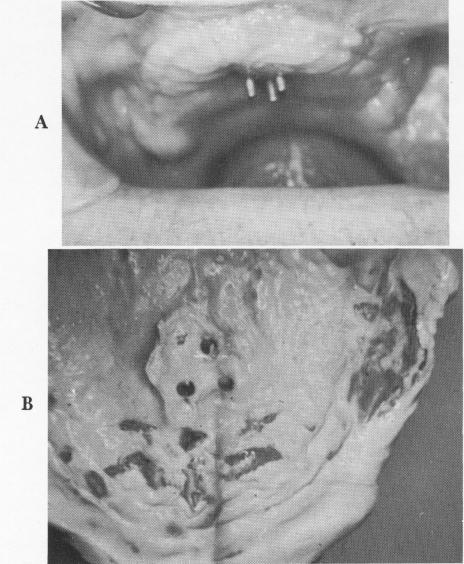

Fig. 12-115. A, Healing around the posts was uneventful. B, The inside of the bite registration block was relined with silicone and a final wax interocclusal record of centric relation was taken.

Fig. 12-117. A, An excessive amount of intermaxillary space existed between both atrophied arches. B, The implant dentures mounted on the articulator.